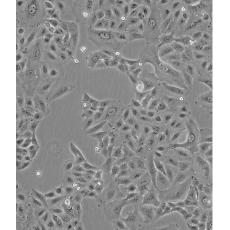

A549/DDP

產(chǎn)品名稱 A549/DDP

中文名稱 人肺腺癌耐順鉑株

生長特性 adherent

形態(tài)特征 epithelial